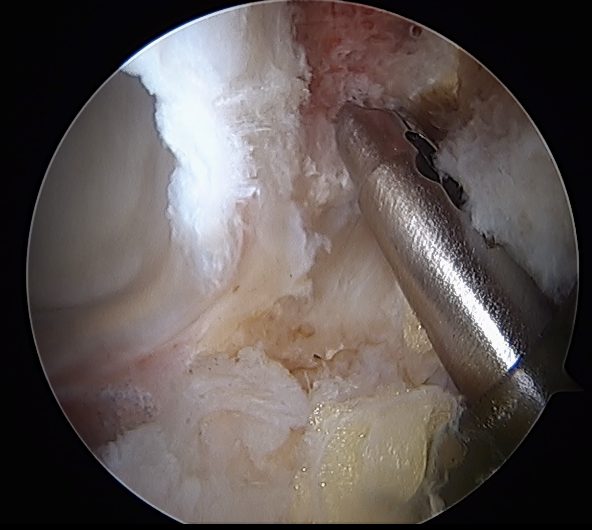

Acetabular rim trim / Acetabuloplasty

Pincer resection

Os acetabuli resection

CAM resection

Capsule

- distal capsule suspension sutures / parachute technique

- T capsulotomy - better for large Cam lesions, needs repair

Placing distal capsule sutures to allow parachute technique / distal capsule suspension to expose Cam

T capsulotomy to expose large Cam at head neck junction